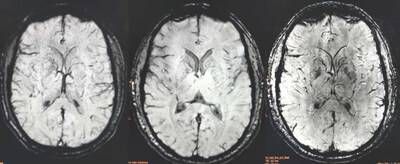

Alzamend Neuro, Inc. (Nasdaq: ALZN) ("Alzamend"), a clinical-stage biopharmaceutical company focused on developing novel products for the treatment of Alzheimer's disease ("Alzheimer's"), bipolar disorder type 1 ("BD"), major depressive disorder ("MDD") and post-traumatic stress disorder ("PTSD"), today announced encouraging pharmacodynamic findings from a brain magnetic resonance spectroscopy ("MRS") analysis conducted in healthy human subjects (N=6) in a trial conducted at Massachusetts General Hospital. The study assessed changes in five key brain metabolites across 18 brain regions when participants received two-weeks of blood bioequivalent and lithium-dose equivalent AL001 or lithium carbonate relative to baseline. Early data suggest AL001 may work like lithium carbonate by selectively impacting brain chemicals where needed, however, AL001 appears to be leaving other, healthy brain chemicals more undisturbed than lithium carbonate, a potentially meaningful tolerability advantage. These interpretations are based solely on qualitative review of all analyses and need to be further statistically confirmed in additional patient populations, the first of which is currently underway.

Brain metabolite concentrations were assessed using ultra-high field high-resolution magnetic resonance spectroscopic imaging (MRSI) in six healthy volunteers following blood-bioequivalent and lithium-dose equivalent 14-day multiple doses of AL001 and lithium carbonate treatments in a randomized, crossover design across 18 brain regions. The five metabolites analyzed were: total creatine (Cr+PCr), glutamate (Glu), glycerophosphocholine plus phosphocholine (GPC+PCh), myo-inositol (Ins), and N-acetylaspartate plus N-acetylaspartylglutamate (NAA+NAAG). Statistical analyses used the Wilcoxon signed-rank test and Hedges' g effect-size measure, with a pre-specified ≥20% absolute threshold to screen for pharmacodynamically relevant signals. The MRS neuroimaging methodology was developed by the lab of Dr. Ovidiu C. Andronesi, the study's principal investigator, Associate Professor of Radiology at Harvard University, and the Director of Multinuclear MR Imaging, Martinos Center for Biomedical Imaging, Department of Radiology, Massachusetts General Hospital, Harvard Medical School. All findings are exploratory, hypothesis-generating, and require confirmation in adequately powered studies.